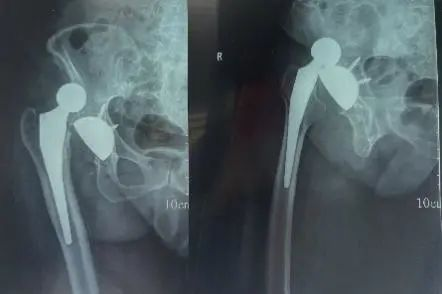

# لماذا يحدث خلع مفصل الورك بعد استبداله؟ وكيف يمكن الوقاية منه وعلاجه؟ يعتبر استبدال مفصل الورك الكلي (THA) إجراءً فعا…